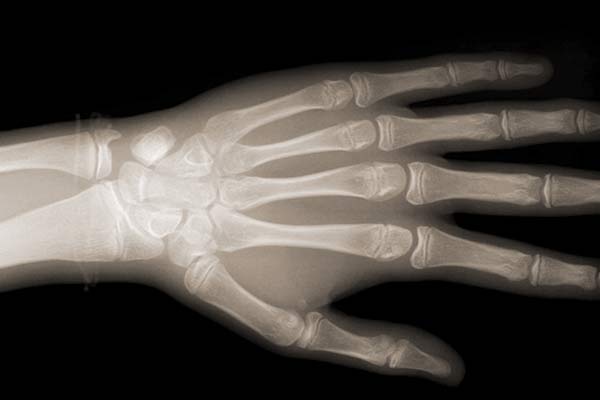

Digitales Röntgen - Handwurzelaufnahme (HWA)

Um den günstigsten Zeitpunkt zur Kieferumformung zu bestimmen ist es bei einzelnen Patienten notwendig, das genaue Knochenwachstumsstadium zu ermitteln. Da das Wachstum des Schädels weitgehend dem des Körpers folgt, erlaubt die Handwurzelaufnahme eine Aussage über die Wachstumssituation des Patienten und das noch zu erwartende Wachstumspotential, so dass die kieferorthopädischen Maßnahmen auch jeweils zum individuell richtigen Zeitpunkt erfolgen können.